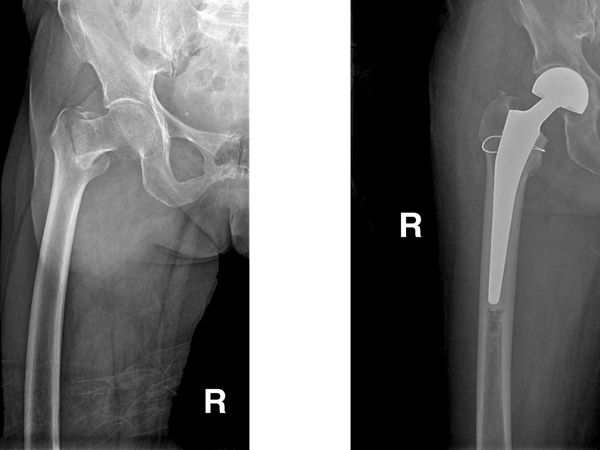

2014-03-21成功實施區(qū)內(nèi)首例九旬高齡股骨粗隆間骨折人工股骨頭置換

我院骨科一區(qū)近日成功為年過九旬的高齡股骨粗隆間骨折患者進行了人工股骨頭置換術(shù)。 93歲高齡的梁婆婆摔倒后,不能站立,家人將她送到了我院進行治療。梁婆婆入住我院骨科一區(qū),醫(yī)師為她進行...閱讀全文